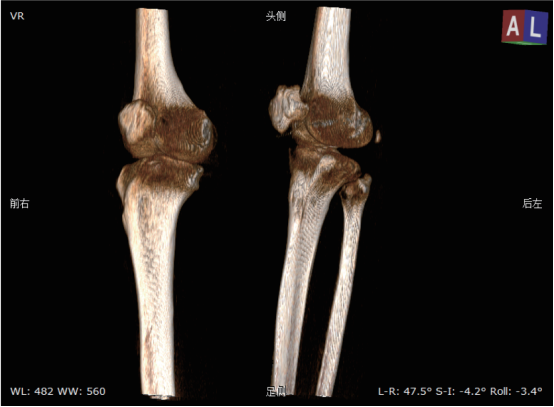

该系统核心优势在于整合动态透视与三维成像技术。在脊柱全长摄影、双下肢负重位检查中,可一次性获取颈椎至骶尾椎的高清全景影像,避免传统分段拍摄的拼接误差,为脊柱侧弯、关节畸形等疾病的力线测量和手术规划提供精准数据。其动态功能成像模块能实时捕捉关节运动状态下的解剖结构变化,清晰显示膝关节屈伸、肩关节活动时的软组织动态,显著提高韧带损伤、关节不稳等隐匿性病变的检出率。